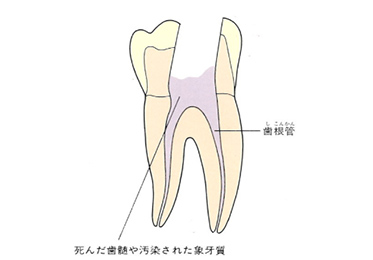

これまで説明してきたように、歯の中には歯髄(シズイ)組織が入っています。いわゆる神経のことです。この神経に虫歯などで細菌感染を起こし、歯根尖まで炎症が波及した状態が、根尖性歯周炎(コンセンセイシシュウエン)です。

上の図にあるように神経の管に入れる薬が根尖(コンセン)まで入っていなかったり、途中までしか入っていなかったり、薬がスカスカだったりするとその空間にばい菌が繁殖して感染を起こします。

この根っこの病気を根尖性歯周炎というのです。そしてこの根尖性歯周炎を治すことを感染根管治療と言います。

根の先を見ると小豆ぐらいの大きさの黒い影が見えます。根の中でばい菌が繫殖し感染を起こすとこのような黒い影ができます。黒い影の部分は膿(ウミ)が貯まっています。こうなると腫れて痛みが出てくるのです。